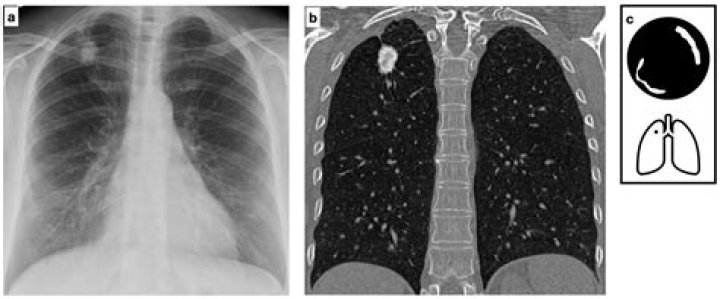

Read JournalLung nodules are usually about 0.2 inch (5 millimeters) to 1.2 inches (30 millimeters) in size. A larger lung nodule, such as one that's 30 millimete...